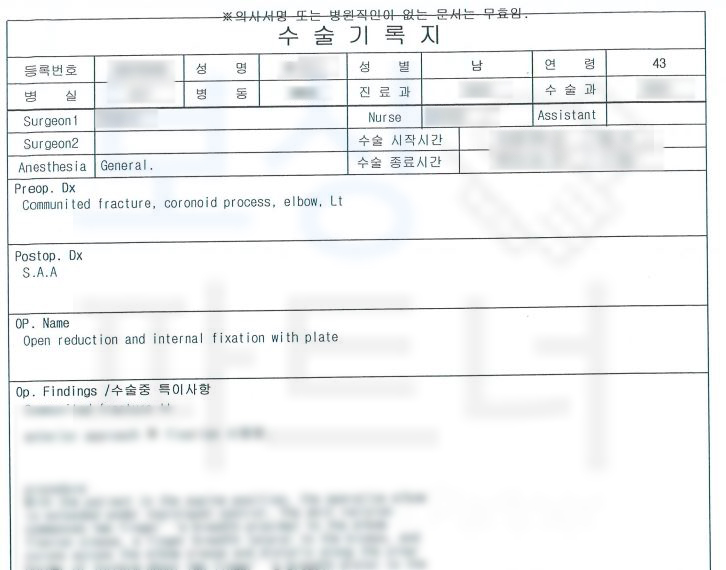

진단서를 보시면

척골 갈고리돌기 의 골절 S52030 팔꿈치골절 진단을 받으셨고 금속 고정술을 시행하셨습니다.